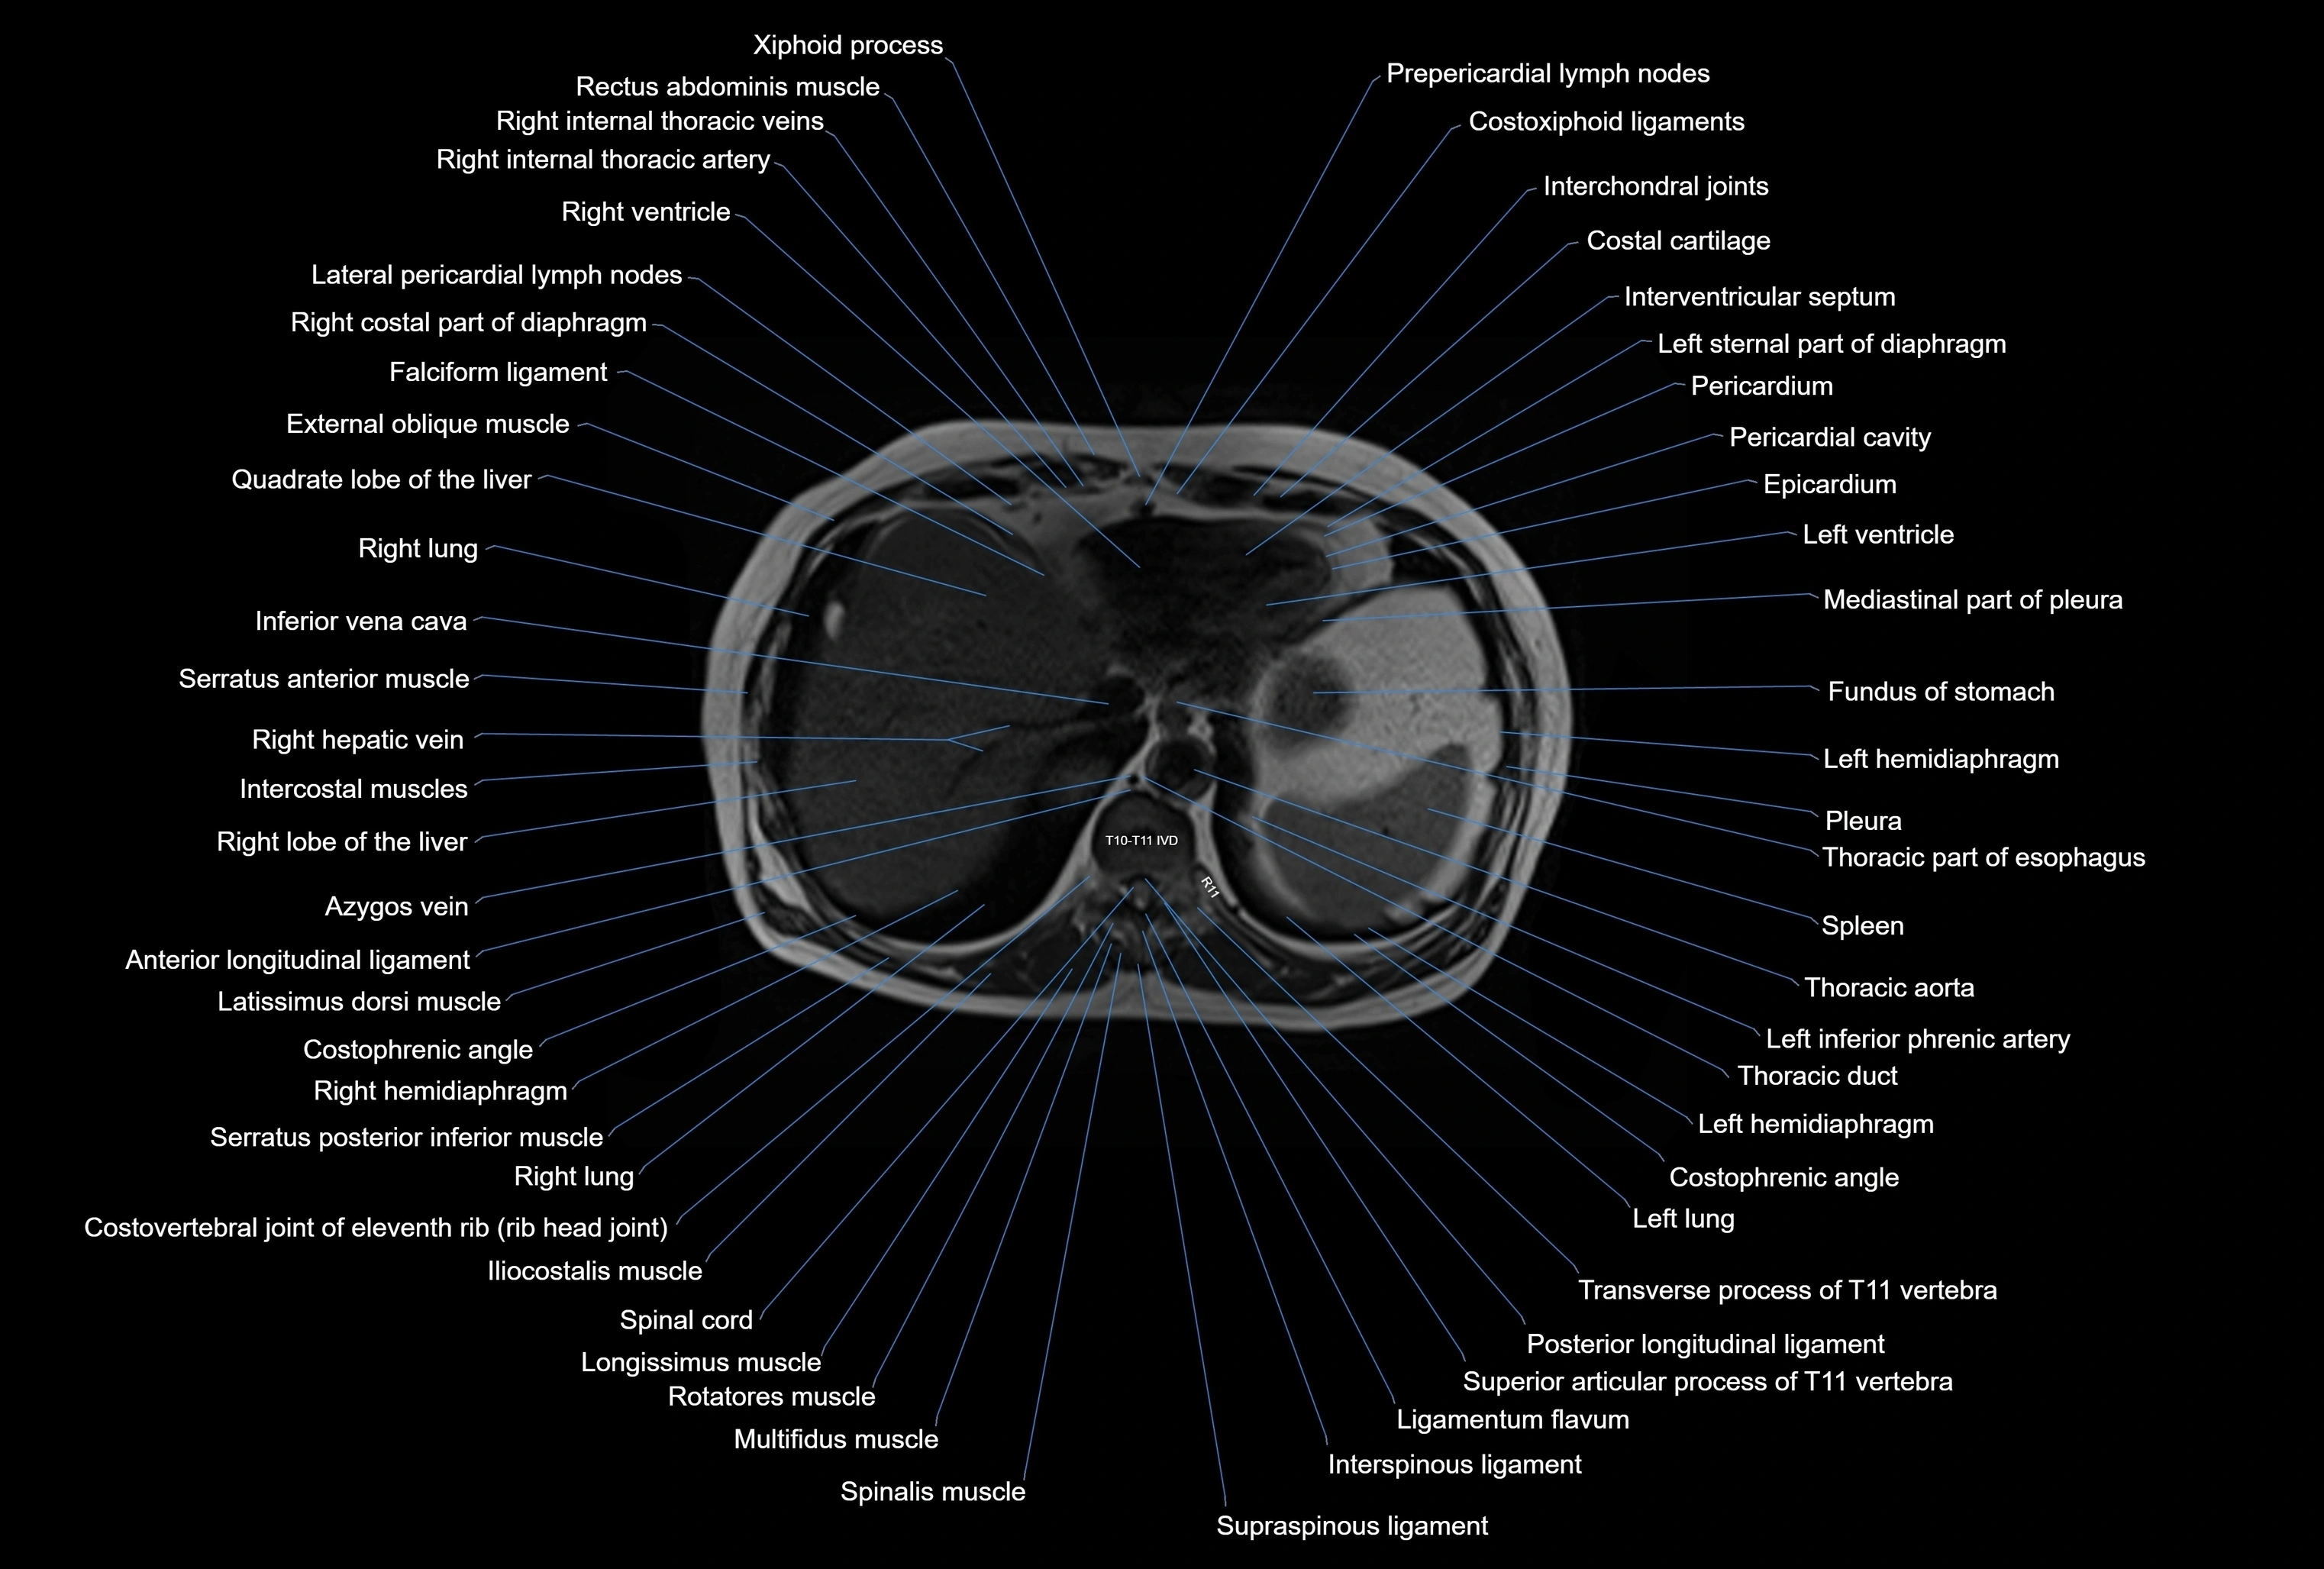

MRI images